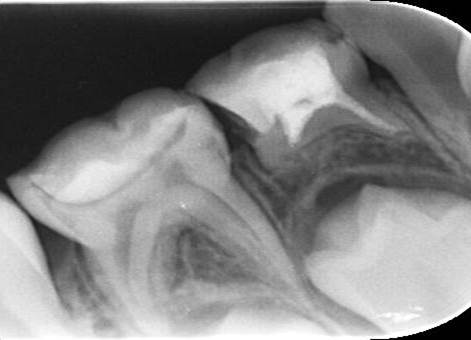

レントゲンを見ると○部分にエックス線透過像が観察されていますので、根尖部に膿瘍があることが分ります。

根管内の消毒を行って、根管充填をおこないました。